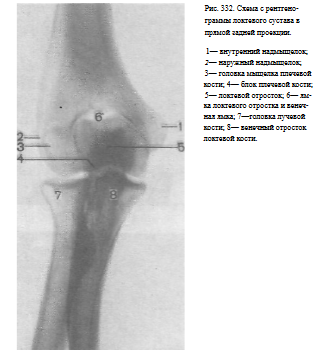

Информативность снимка. На рентгенограмме выявляются дистальный конец плечевой кости, ее суставная поверхность, образованная головкой и блоком, рентгеновские суставные щели плечелучевого, плечелоктевого и проксимального лучелоктевого суставов, головка лучевой кости, локтевой и венечный отростки локтевой кости и проксимальные отделы диафизов лучевой и локтевой костей (рис. 332).

Критерием правильности укладки является отображение рентгеновских суставных щелей плечелоктевого и плечелучевого суставов в виде лентовидной извилистой полосы просветления.